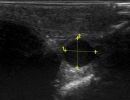

Πολλές αλλοιώσεις και παθήσεις μπορούν να απεικονιστούν υπερηχογραφικά και να μελετηθούν αξιόπιστα με τη βοήθεια του Έγχρωμου Doppler και της Ελαστογραφίας .

- Αιμαγγειώματα, αγγειοδυσπλασίες (αγγειακού τύπου βλάβες)